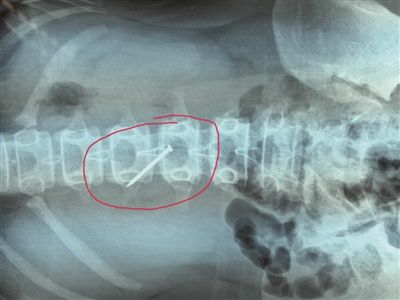

長約4厘米的鐵釘被取出時,已刺穿13歲女生的胃壁。 朱鼎兆 攝

一根長近4厘米的鐵釘在胃里會怎么樣?29日下午4時許,在淮安市婦幼保健院,該院小兒科醫(yī)生就從宿遷泗陽一名13歲女生小軒(化名)的胃里成功取出一根長約4厘米的鐵釘,而此時,這根鐵釘已經刺破了小軒的胃壁。